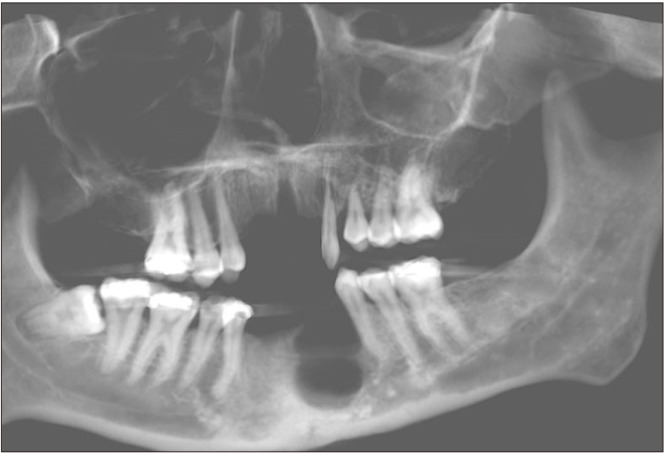

Neurofibromatosis type 1 (NF1) is an autosomally dominant tumor suppressor syndrome and multisystem disease. Central giant-cell granulomas (CGCGs) can be seen in patients with NF1. A 21-year-old female was diagnosed with two CGCGs, one in the mandible and then one in the maxilla, in a 7-year period. Increased incidence of CGCGs in NF1 patients was thought to be caused by an underlying susceptibility to developing CGCG-like lesions in qualitatively abnormal bone, such as fibrous dysplasia. However, germline and somatic truncating second-hit mutations in the NF1 gene have been detected in NF1 patients with CGCGs, validating that they are NF1-associated lesions. Oral manifestations in patients with NF1 are very common. Knowledge of these manifestations and the genetic link between NF1 and CGCGs will enhance early detection and enable optimal patient care.